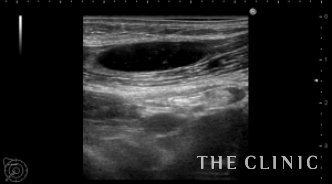

ヒアルロン酸豊胸は乳腺下(大胸筋と乳腺の間)に注入しますが、この方は大胸筋の中に注入されていました。

ヒアルロン酸によるしこりは、ヒアルロン酸溶解注射(ヒアルロニダーゼ)で分解すれば吸引除去が可能ですが、確実にしこり内に注射するためにはエコー下で行う必要があります。

画像は、しこりの中に注射針を穿刺したところと、ヒアルロニダーゼを注入しているところです。